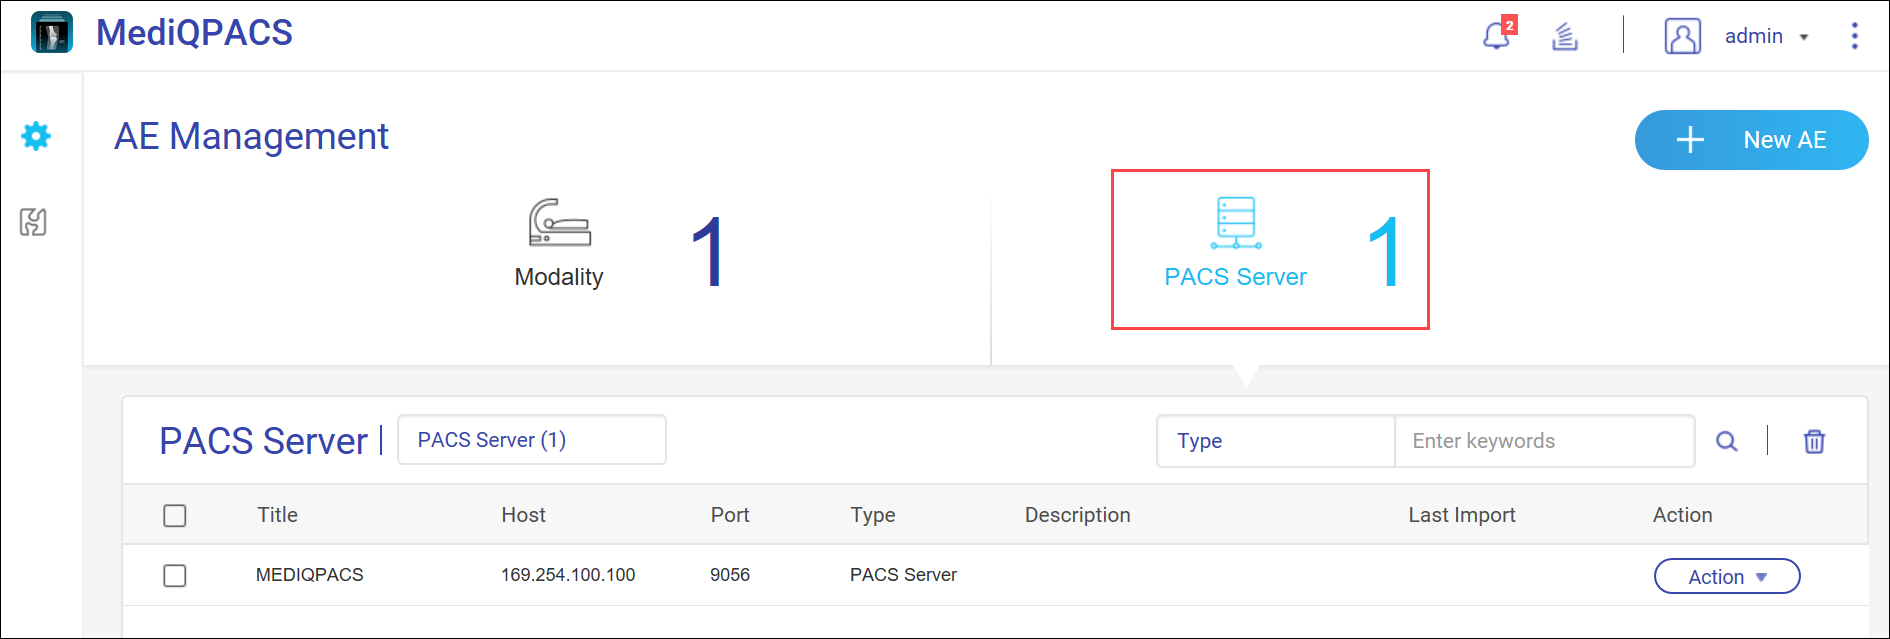

应用实体 (AE) 管理

在 DICOM 中,应用实体 (AE) 表示 DICOM 网络中的端点系统或程序,例如设备或 PACS 服务器。将 NAS 配置为 PACS 服务器时,将它视为一种 AE。

在 MediQPACS 的“AE Management”(AE 管理)屏幕中,用户可以在本地或外部网络上添加、编辑、删除、搜索和测试其他 AE 的连接。

单击  以查看“AE Management”(AE 管理)屏幕。